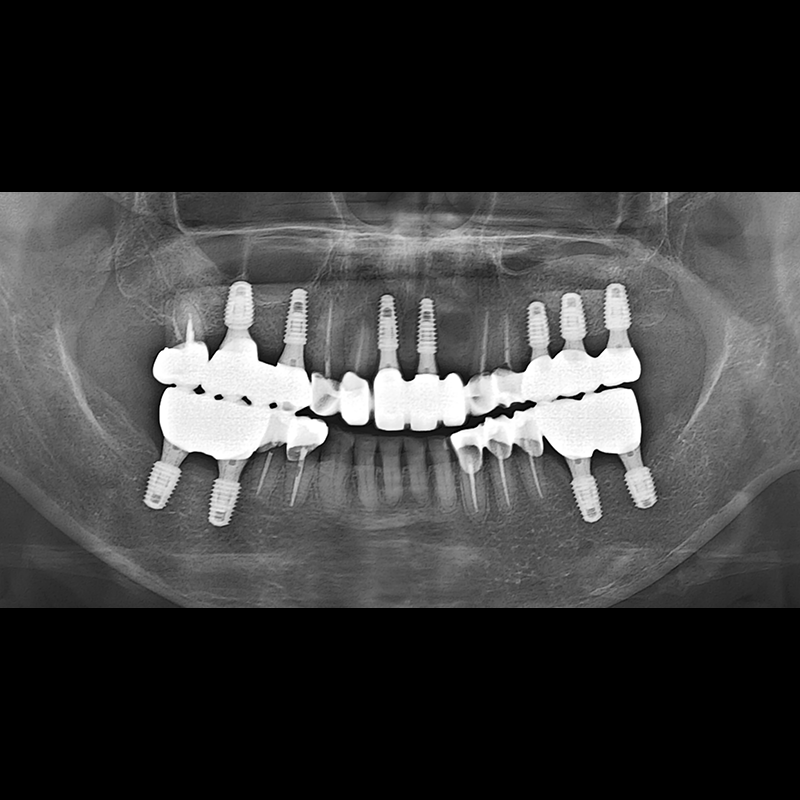

BEFORE AFTER

种植牙前后的照片 2025.05.30

在缺失的牙齿部分和难以挽救的牙齿位置植入了种植牙。